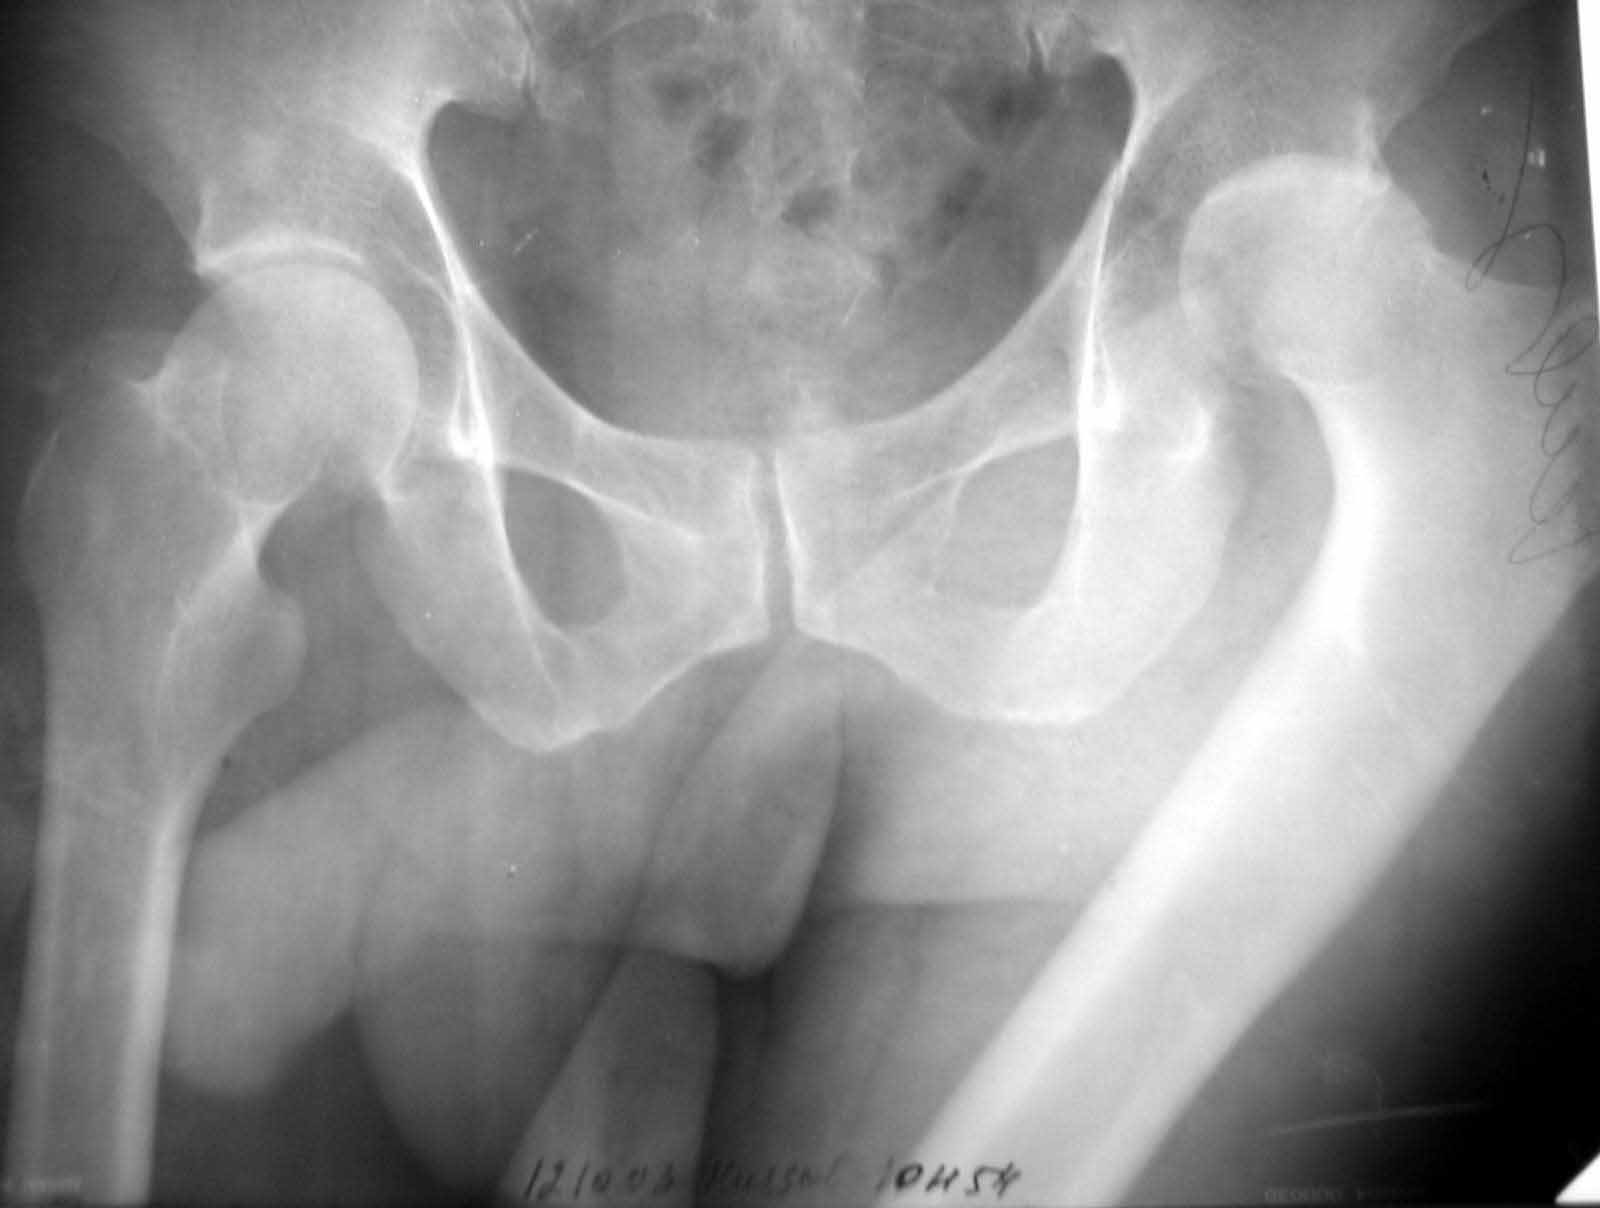

Больной Н. 54 лет. Поступил в подвздошным вывихом левого бедра. После попытки закрытого одномомендного вправления 2 мес. на скелетном вытяжении. На Rg контроле видимость вправления, на КТ - неустраненный вывих. По причине тяжелой соматической патологии открытое вправление и репозицию заднего края выполнить не представляется возможным. Вправление аппаратом внешней фиксации, КТ - этапах вправления - дефект заднего края. Что вы нам посоветуете по дальнейшей тактике? Больной Н. 54 лет. Диагноз: Закрытый оскольчатый перелом заднего края вертлужной впадины слева, подвздошный вывих левого бедра. Ушиб грудной клетки. ИБС. Стенокардия напряжения. ФКI-II. Постинфарктный кардиосклероз. Артериальная гипертония II степени, риск IV. НI. Состояние после аорто-коронарного шунтирования. Хронический бронхит. ДНI.Травма в результате ДТП. Больной лечился консервативно - закрытое одномоментное ручное вправление, фиксация скелетным вытяжением в течение 2 месяцев. На контрольных обзорных рентгенограммах таза в динамике: головка бедра располагается в проекции вертлужной впадины, суставные поверхности конгруентны. После снятия скелетного вытяжения выполнялся КТ - контроль тазобедренного сустава, на котором обнаружен неустраненный задний вывих бедра. Через 2 месяца наложена передняя тазовая и бедренная опоры. По причине тяжелого соматического состояния не представлялось возможным выполнить открытое вправление вывиха и остеосинтез заднего края. Представлен КТ- контроль на этапе вправления, на котором виден дефект заднего края вертлужной впадины.

Я не понял как отправлять несколько файлов для графического приложения. Отправляю прямую проекцию в день травмы, после "вправления" на вытяжении и КТ. На данный момент головка бедра во впадине. КТ во вправленном состоянии отправлю по возвращении